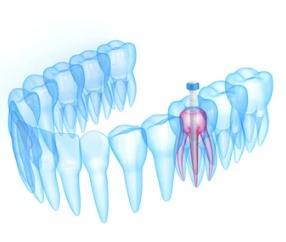

Post and core therapy

Post and core therapy involves placing a metal or fiber post in a root canal-treated tooth to support a crown, restoring its strength and function. This procedure helps ensure the longevity and stability of the tooth.